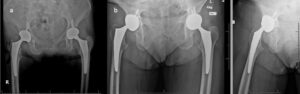

image_3_488